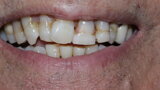

Figure 2 Full face before treatment